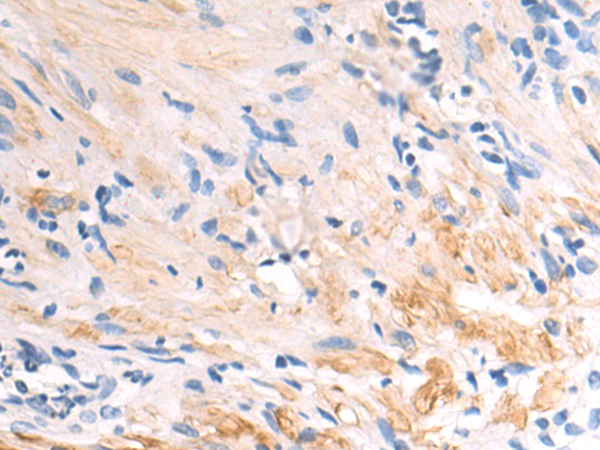

分类: 科研抗体货号: P04339别名: M130; MM130应用: IHC反应种属: Human